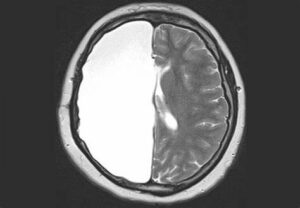

- Beyninizin yarısının ameliyatla alınması sonucunda hafızanız ve karakteriniz değişmeden hayatınıza devam edebilirsiniz.